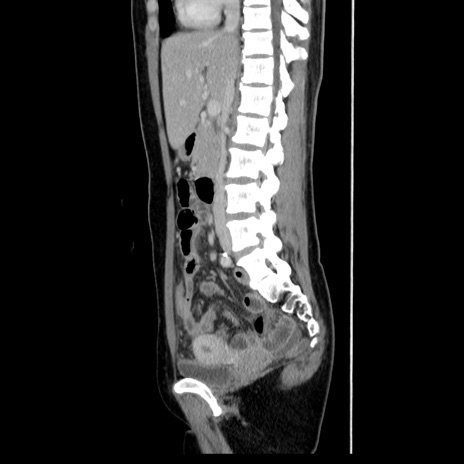

症例39(矢状断像)

【症例】40歳代女性

【主訴】上下腹部痛

【現病歴】2日目から下腹部痛あり。夜間は痛みで眠れなかった。昨日より上腹部痛と下痢が出現。臥位で痛みは軽快したため、休んでいた。本日になって臥位でも立位でも痛みが強くなってきたため救急要請。

【既往歴】子宮内膜症

【身体所見】部:平坦・軟、左上下腹部に圧痛あり、反跳痛あり。

【データ】WBC 21800、CRP 26.78

CT